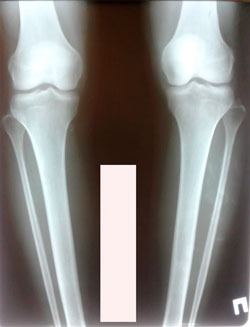

Исходник - 24 года.

Дата операции - 25.011.2020

Диагноз: Варусная деформация обеих голеней + Ротация с обеих сторон.